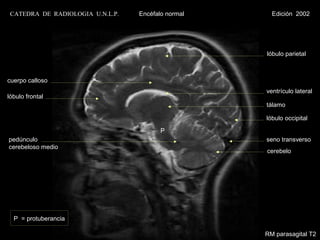

RM parasagital T2

CATEDRA DE RADIOLOGIA U.N.L.P.   Encéfalo normal     Edición 2002

lóbulo parietal

cuerpo calloso

ventrículo lateral

lóbulo frontal

tálamo

lóbulo occipital

P

pedúnculo                                           seno transverso

cerebeloso medio

cerebelo

P = protuberancia